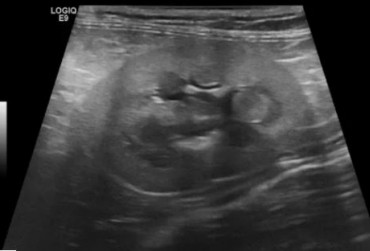

Torbiel pierwotna jest rzadką wadą rozwojową występującą u człowieka, psa, kota i konia. W niniejszym artykule opisano przypadek torbieli pierwotnej jelita prostego u dziewięcioletniego kota rasy Manx, u którego występowały przewlekłe zatwardzenia. W badaniu rektalnym i radiograficznie stwierdzono obecność miękkiego guza dogrzbietowo i bocznie od jelita grubego. Badaniem ultrasonograficznym i w tomografii komputerowej uwidoczniono dobrze odgraniczoną, cienkościenną torbiel, częściowo zamykającą światło kanału miednicy. Torbiel usunięto chirurgicznie z dojścia okołoodbytowego. Nie stwierdzono połączenia torbieli ze ścianą prostnicy. Badanie histopatologiczne potwierdziło postawione podejrzenie torbieli pierwotnej. Po wykonanym zabiegu objawy kliniczne całkowicie ustąpiły.